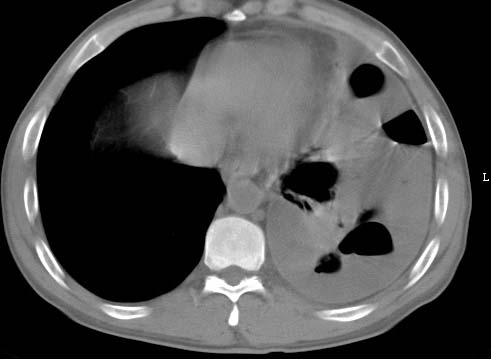

标题: CT10145:男性,30岁,活动后气促2月余.隔疝伴胸腔积液.右上肺结 [打印本页]

男性 病人 30岁,活动后气促2月余.隔疝伴胸腔积液.右上肺结核!

左侧胸腔积液,并胸腔内见多个含液 气组织,并相互重叠。影像特征很特殊,应该是“膈疝”。支持!

左侧膈疝,及左侧胸水,双上肺结核。